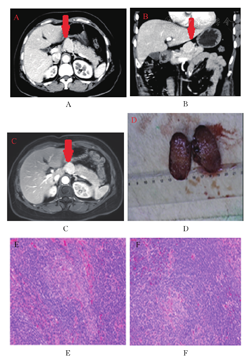

患者女性,54岁,因"反复左上腹隐痛1年,发现胰腺占位1月"入院。患者于1年前开始无明显诱因出现左上腹间断性隐痛不适,疼痛无向他处放射,无恶心、呕吐,无长期腹泻、便秘,无长期发热、感冒等病史。入院前1月当地医院腹部彩超提示:胰腺区低回声,MR检查见"胰腺颈体部占位性病变,考虑胰岛细胞瘤可能"。入院后查体未见明显异常。实验室检查肝肾功能、电解质、血淀粉酶、血胰岛素、血糖、肿瘤指标均正常范围,HIV抗体阴性。影像学CT(图1A、图1B)、MRI(图1C)提示腺体部见一直径约3.5 cm肿物,动脉期均匀强化,血供丰富,密度高于胰腺组织。

考虑患者无功能胰岛细胞瘤可能性大,行剖腹探查可见胰腺体部上方有一椭圆形红色实性包块紧密生长,肿物直径约3.5 cm,质地硬,有包膜,与胰腺组织界限清晰。手术完整切除包块,术中冰冻提示淋巴结反应性增生。术后标本提示淋巴结1个,镜下淋巴结节结构基本保存,皮质区淋巴滤泡及副皮质区淋巴细胞增生,滤泡生发中心萎缩,伴透明血管穿入现象,套区淋巴细胞同心圆状围绕生发中心呈"洋葱皮"样结构。免疫组化提示CD3及CD5(T细+),CD20(B细胞+),CD21(滤泡树突细胞阳性),CyclinD1(-),Ki-67(滤泡生发中心高表达)(图1D、图1E、图1F)。结合免疫组化,符合透明血管型Castleman病。患者术后恢复良好,1周后出院,术后左上腹隐痛症状未再出现,随访期间无复发。